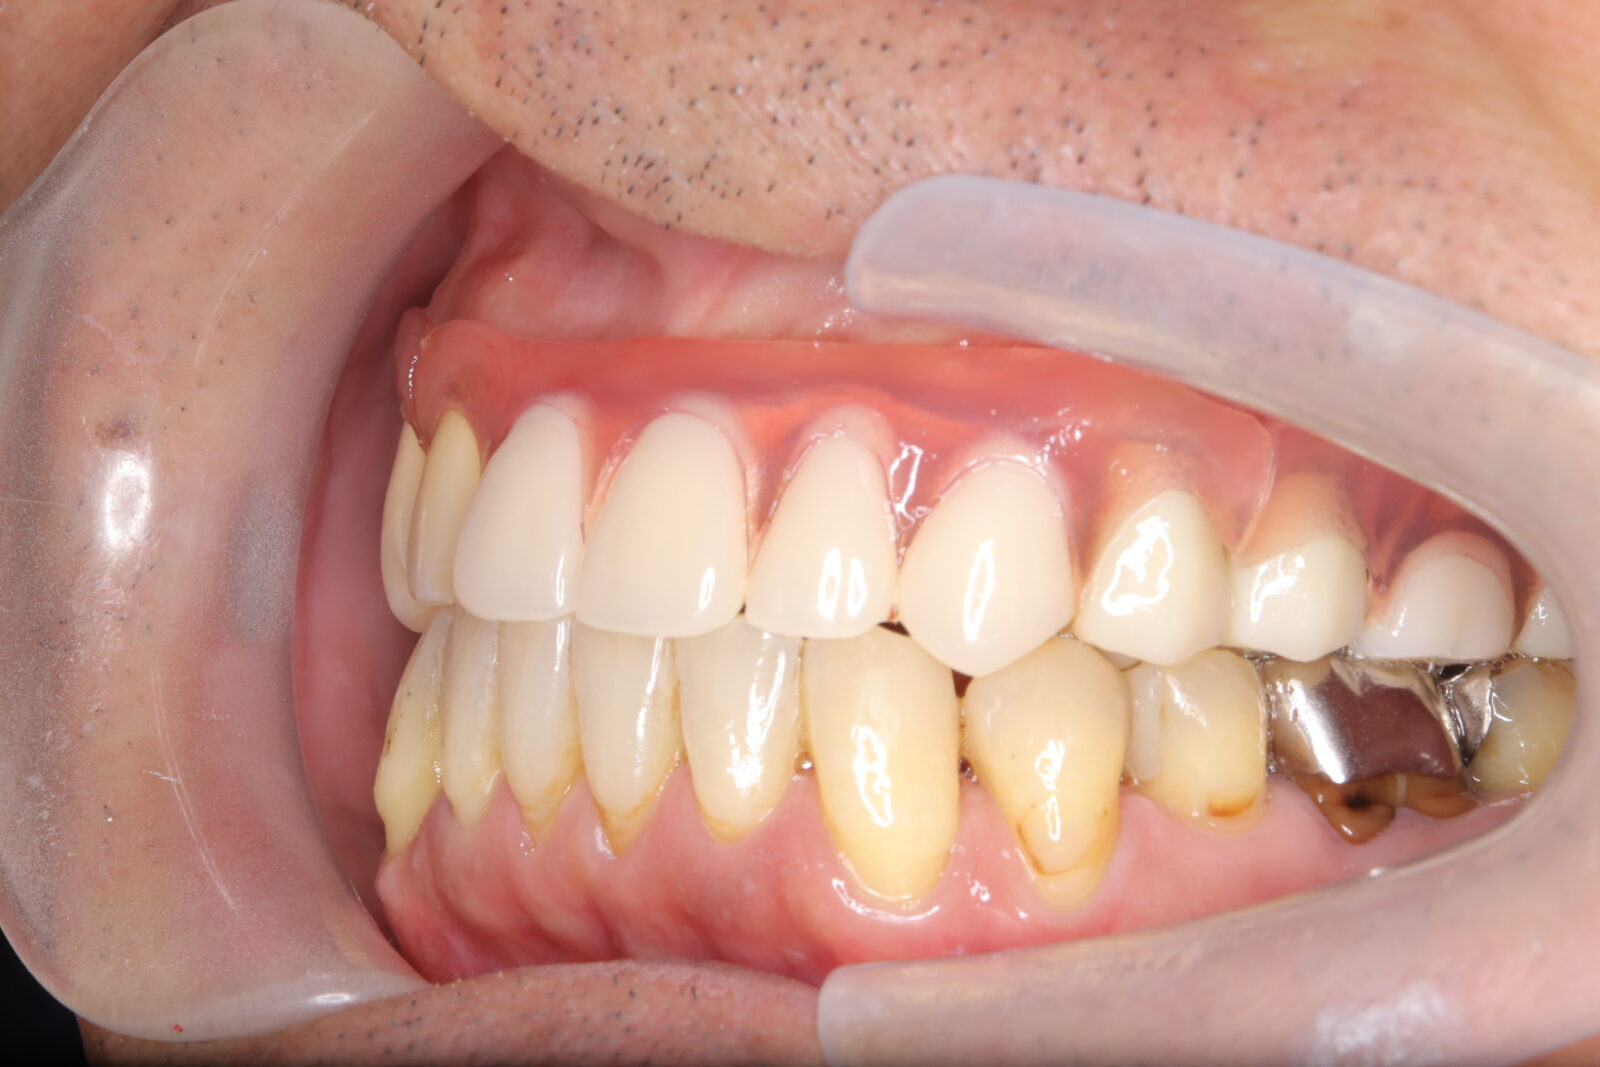

職業柄抜歯をすることができない患者様の症例

職業柄抜歯をすることができないため、小臼歯も親知らずも非抜歯の矯正となりました。 それでは歯を並べるためのスペースを確保できない。歯根の形状を分析し、可能な限り歯冠修復で前歯のサイズを小さくして、歯を動かすためのスペースを作り矯正をスタートした。 下顎前歯歯並びきれないこと、理想的な噛み合わせの獲得は難しいことをご理解いただき治療スタートした。 終了時に初期時の不自由がないことを確認済み。